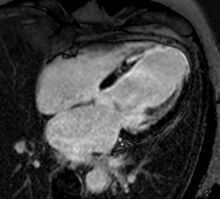

Myocardial infarction. Imaging in the 4-chamber plane. Left: Inversion recovery LGE sequence. Right: Corresponding cine sequence. This shows a chronic infarction with akinetic apex and transmural scar. Mitral regurgitation is also present.